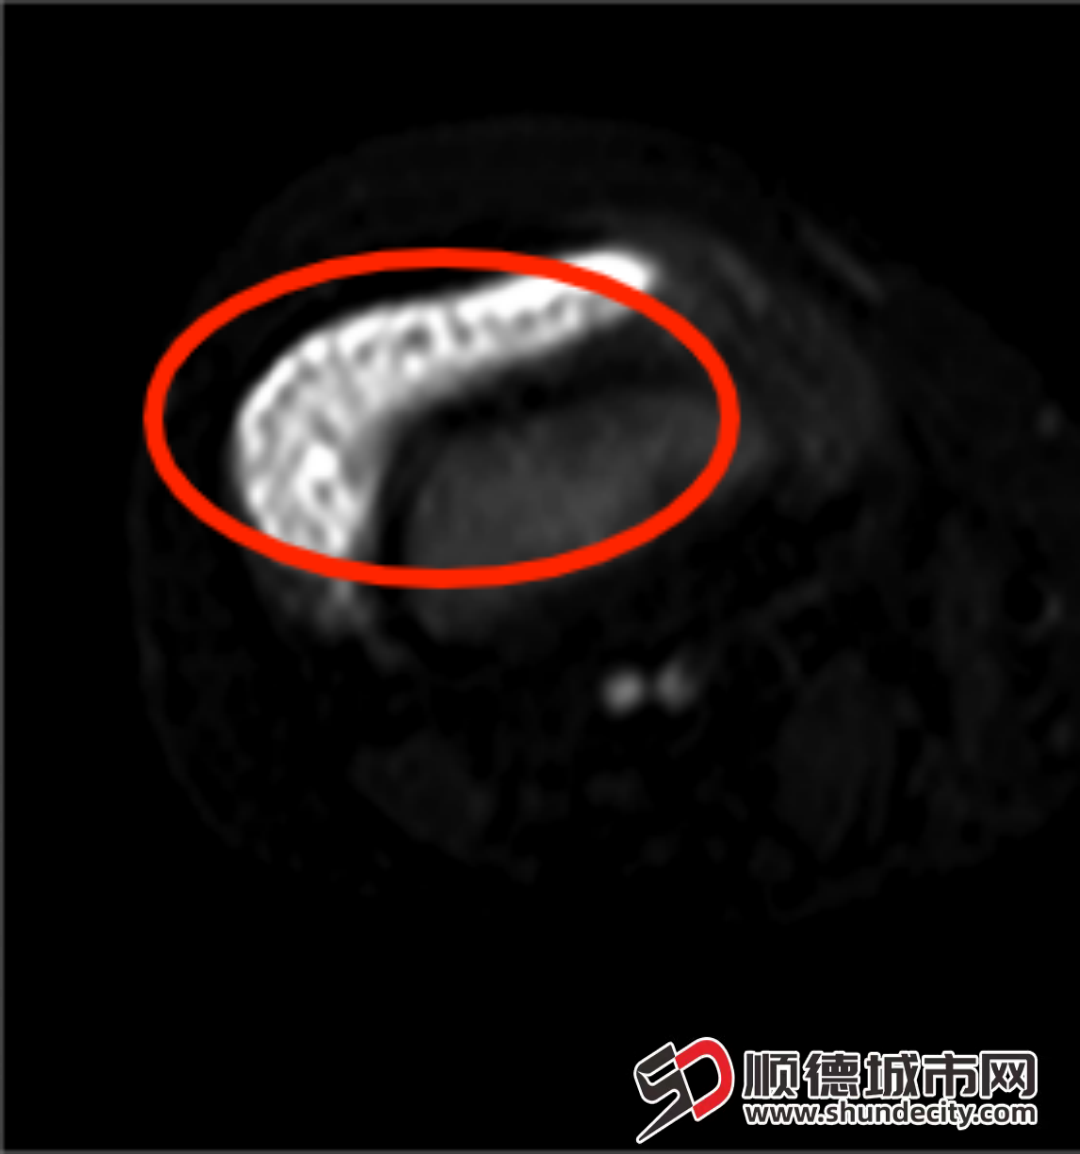

小小的关节内堆积着“米粒”。

膝关节MRI影像可见密密麻麻的滑膜组织。